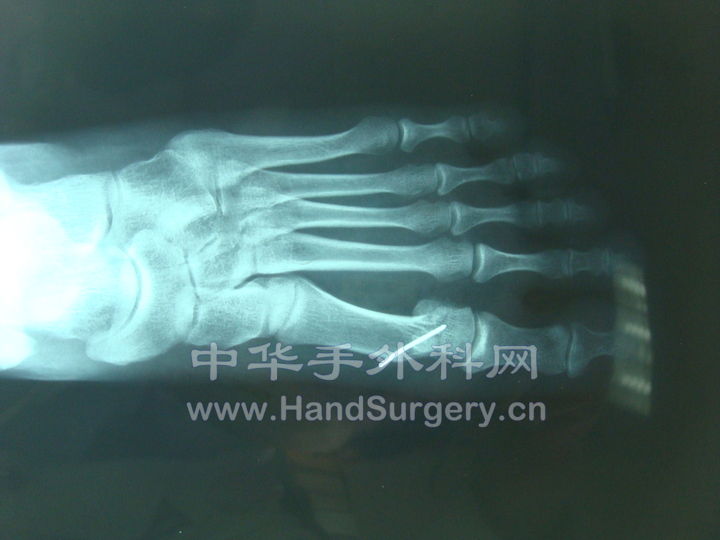

这是一个拇外翻的线片。scarf+Akin术前,术后。

chevron截骨